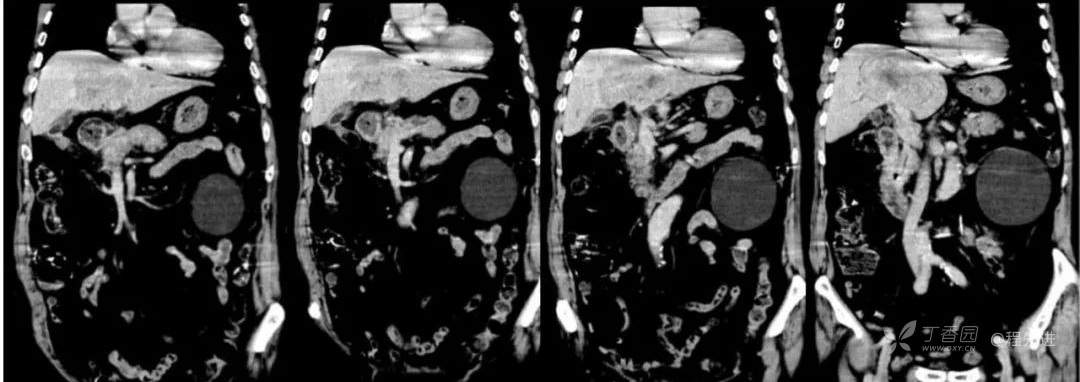

简要病史:因胸部不适入院,胸部CT示:肺部感染性病变;腹部CT示:肝门区占位性病变